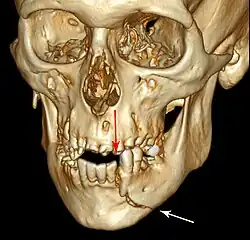

Essa lesão envolve o osso alveolar e pode se estender além do alvéolo. [7] [8] Existem 5 tipos diferentes de fraturas alveolares:

- Fratura comunicada da parede do alvéolo

- Fratura da parede da cavidade

- Fratura dento-alveolar (segmentar)

- Fratura da maxila: Fratura Le Fort, fratura zigomática, erupção orbital

- Fratura da mandíbula

As lesões traumáticas envolvendo os alvéolos podem ser complicadas, pois não ocorrem de forma isolada, muitas vezes se apresentando juntamente com outros tipos de lesões do tecido dentário.

Sinais de fratura dento-alveolar:

- Elementos dentários movendo-se juntos como um segmento e normalmente são deslocados.

- Hematomas na gengiva inserida.

- Gengiva em toda a linha de fratura frequentemente lacerada[9].

Investigação: Requer mais de uma visualização radiográfica para identificar a linha de fratura.

Tratamento: Reposicionar os dentes deslocados sob anestesia local e estabilizar o segmento móvel com uma tala por quatro semanas; suturar quaisquer lacerações de partes moles.